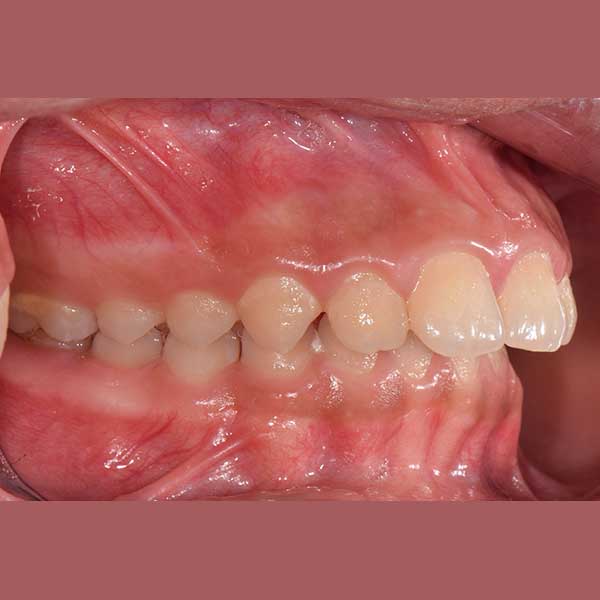

BEFORE

راجعتني هذه الآنسة الصغيرة برفقة والدتها، وكانت الشكوى الرئيسية هي بروز الأسنان بشكل كبير، مما أثر سلباً على نفسيتها وثقتها بابتسامتها، بالإضافة إلى تأثيره على نطق بعض الحروف.

بعد الفحص الدقيق، وجد الدكتور خالد الكاتب أن الأسنان العلوية متقدمة على السفلية بمسافة كبيرة (8 مم)، وأن السبب الجذري للمشكلة هو تراجع الفك السفلي. ونظراً لصغر عمر المراجعة ورفض الأهل لخيار قلع الأسنان، تم وضع خطة علاج ذكية تعتمد على تقديم الفك السفلي للأمام باستخدام جهاز وظيفي ثابت، وهو خيار مثالي في مرحلة النمو.